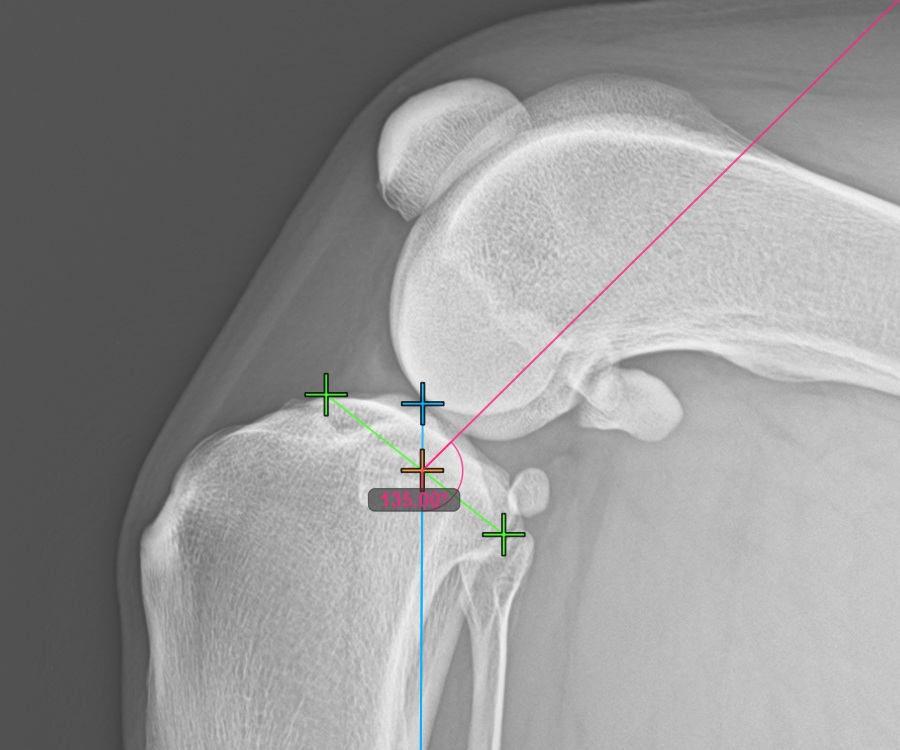

To complete the TTA Rapid variant of TTA measurement procedure mark the most dorsal point of the Crista Tibiae (Tuberositas Tibiae). The distance between the Tuberositas Tibiae and the automatic TTA Rapid helper lines is the required adjustment for the TTA procedure.

The image below depicts the usual placement of the tibial tuberosity, the most prominent point of the tibial crest.